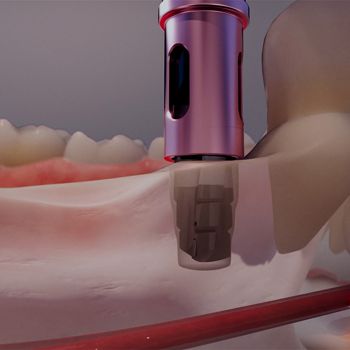

Soluciones para Espacios Horizontales Reducidos

Narrow GM

Aporte confiabilidad a su práctica con la próxima generación de soluciones estéticas inmediatas para espacios interdentales reducidos y disponibilidad ósea.

El Helix® GM Narrow de Ø2.9mm proporciona una solución inmediata de diámetro pequeño que ofrece simplicidad y confiabilidad en el protocolo de tratamiento, independientemente de si se utilizan técnicas guiadas o no guiadas. El sistema fue diseñado para brindar mayor confianza y flexibilidad en casos con espaciado interdental limitado.

Espacios Estrechos

Diámetro de 2.9mm

Superficie Acqua

Concepto Easyguide